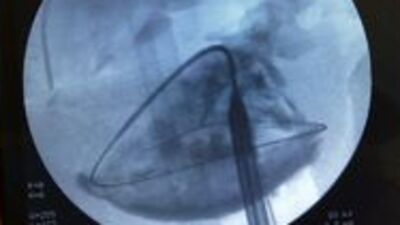

Sol tarafında ağrı şikayetiyle, sağlık merkezlerine başvuran S.İ. isimli hastaya böbreğinde kist olduğu, böbreğinin alınması gerektiği bildirildi. Ancak bu durumu kabul etmeyen hasta, son olarak Medical Park Bursa Hastanesi Üroloji uzmanı Doç. Dr. Özcan Atahan'a başvurdu. Doç Dr. Atahan, açık veya laparoskopik ameliyatı reddeden hasta S. İ.'ye, normalde böbrek taşlarında kullanılan bir yöntem olan mikroperkütan yöntemi önerdi. Buna göre böbrek alınmadan ciltten bir iğne ile kist içine girilmesi, ardından bu deliğin genişletilerek, aynen böbrek taşında olduğu gibi bir ucu ciltte diğer ucu kist içinde bir boru konularak, kistin içindeki kız veziküllerin boşaltılması ve kist duvarının koter ile yakılması uygulaması gerçekleştirilecekti.

Hasta S.İ. perkütan yöntemi kabul etti. Bunun üzerine hastaya Üroloji uzmanı Doç. Dr. Özcan Atahan tarafından dünyada ikinci, Türkiye'de ise ilk defa gerçekleştirilen mikro perkütan yöntemi kullanılarak böbrek kist hidatik hastalığı, güvenli bir şekilde hastaya en az zarar verilerek başarılı bir şekilde tedavi edildi. Ameliyat sırasında ve sonrasında hastada herhangi bir yan etki gözlenmedi. Hasta S.İ yapılan tedavinin ardından ertesi gün hastaneden taburcu edildi.

"Koyun ve sığır yetiştiriciliğinin sık olduğu Türkiye, Yeni Zelanda, Avustralya, Kuzey Amerika, Kuzey Avrupa ve Doğu Afrika'da sık olarak görülmektedir. Komplike olmamış kistler için cerrahi çıkarılma, tedavi seçeneği olmakla birlikte beyin, kemik ve birden çok sayıdaki kistlerde tedavi olarak ağızdan albendazole ilacı verilmelidir. Böbrek hidatidozu için perkütan yani cilt yolu ile drenaj ve alkol instillasyonu da güvenli ve en az zarar veren tedavi seçenekleri arasındadır. Bu ameliyatta böbrekte yerleşmiş 12 cm büyüklüğünde bir kist hidatik olgusu, ciltten girilerek böbrek taşına benzer yöntemle böbreğin alınmasına gerek kalmaksızın, başarılı bir şekilde yapıldı. Ayrıca bu yöntem Türkiye'de ilk kez uygulandı"